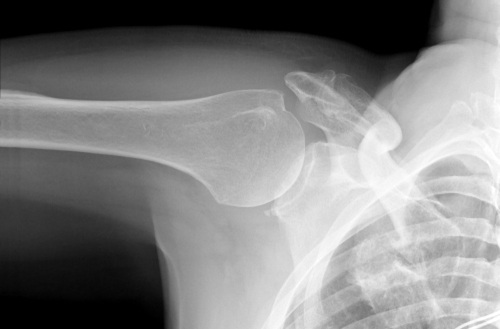

Ett brutet nyckelben (nyckelbensfraktur) är ett vanligt...